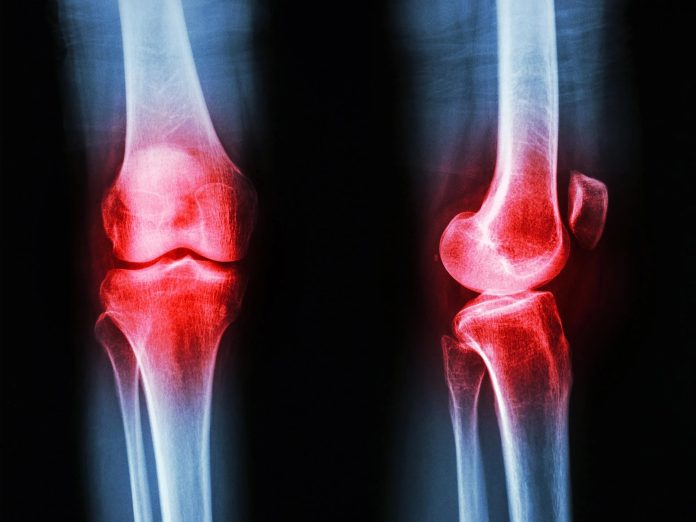

صدمه غضروف، اضافه وزن و انحراف زانو؛ عوامل بروز آرتروز

فوق تخصص جراحی زانو و عضو هیأت علمی دانشگاه علوم پزشکی مشهد با اشاره به عوامل بروز آرتروز گفت: صدمه غضروف، افزایش ساییدگی مفصل، اضافه وزن، انحراف زانو و برخی عفونتها میتواند آغازگر این بیماری باشد.

دکتر هادی مخملباف، جراح زانو و دانشیار گروه ارتوپدی دانشگاه علوم پزشکی مشهد اظهار کرد: آرتروز به معنی ساییدگی مفصل است. در این بیماری بدن قادر به بازسازی غضروف تخریبشده نیست و به تدریج درد و محدودیت حرکتی ایجاد میشود.

وی افزود: از آنجا که غضروف زانو از مایع مفصلی تغذیه میکند، هرگونه اختلال در عملکرد مینیسک یا مایع مفصلی، تخریب غضروف را تسریع میکند. بیماریهایی مانند آرتریت روماتوئید، نقرس و هموفیلی نیز با درگیری پرده سینوویال، روند آرتروز را تشدید میکنند.

این فوق تخصص ارتوپدی با اشاره به دو نوع آرتروز توضیح داد: آرتروز اولیه بدون علت زمینهای مشخص رخ میدهد، اما آرتروز ثانویه بهدنبال شکستگیهای داخل مفصل، آسیبهای لیگامانی و بیماریهای التهابی ایجاد میشود.

وی خاطرنشان کرد: از دیگر عوامل ایجاد آرتروز میتوان به اضافه وزن، انحراف زانو (پای پرانتزی یا پای ایکس)، صدمات غضروفی و عفونتها اشاره کرد. اضافه وزن یکی از عوامل مهم است و در صورت وجود آن، درمانهای دارویی و فیزیوتراپی بهتنهایی پاسخگو نخواهند بود.